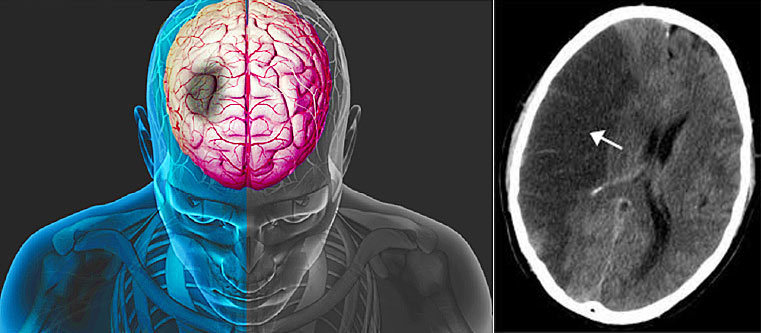

Điện tâm đồ của bệnh nhân rung nhĩ |

Chẩn đoán xác định rung nhĩ bằng điện tâm đồ - đây là một xét nghiệm thường quy. Ngoài ra rung nhĩ có thể được phát hiện nhờ các thiết bị di động gắn trên người bệnh nhân để theo dõi nhịp tim trong khoảng thời gian dài như Holter điện tâm đồ. Bệnh nhân được đeo Holter điện tâm đồ theo dõi nhịp tim trong khoảng từ 1-7 ngày có khi vài tuần. Các thiết bị này giúp ghi lại nhịp tim cả ngày lẫn đêm qua đó cung cấp những thông tin chính xác về biến thiên nhịp tim kể cả khi hoạt động lẫn khi nghỉ ngơi. Điều trị rung nhĩ cần được bắt đầu ngay khi xác định được chẩn đoán.